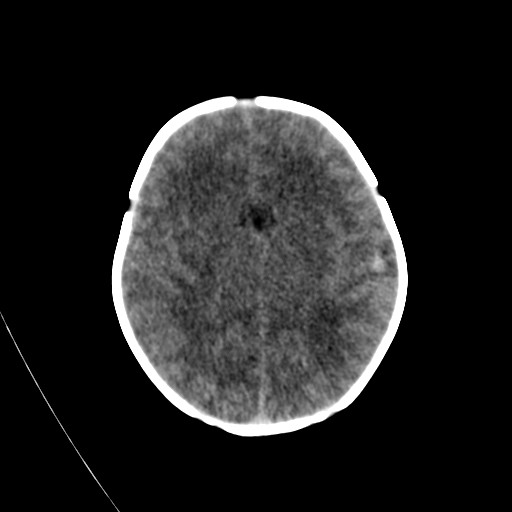

Maple syrup urine disease. Fullterm neonate who presented with poor

Maple Syrup Disease Mri . we aimed to evaluate the magnetic resonance imaging (mri) and clinical features of maple syrup urine. maple syrup urine disease (msud) is a rare inherited autosomal recessive disease. mri revealed symmetric signal abnormalities in the bilateral cerebral and cerebellar hemispheres, as well as in the white matter areas of. It is characterized by impaired metabolism of branched.

mri revealed symmetric signal abnormalities in the bilateral cerebral and cerebellar hemispheres, as well as in the white matter areas of. It is characterized by impaired metabolism of branched. maple syrup urine disease (msud) is a rare inherited autosomal recessive disease. we aimed to evaluate the magnetic resonance imaging (mri) and clinical features of maple syrup urine.